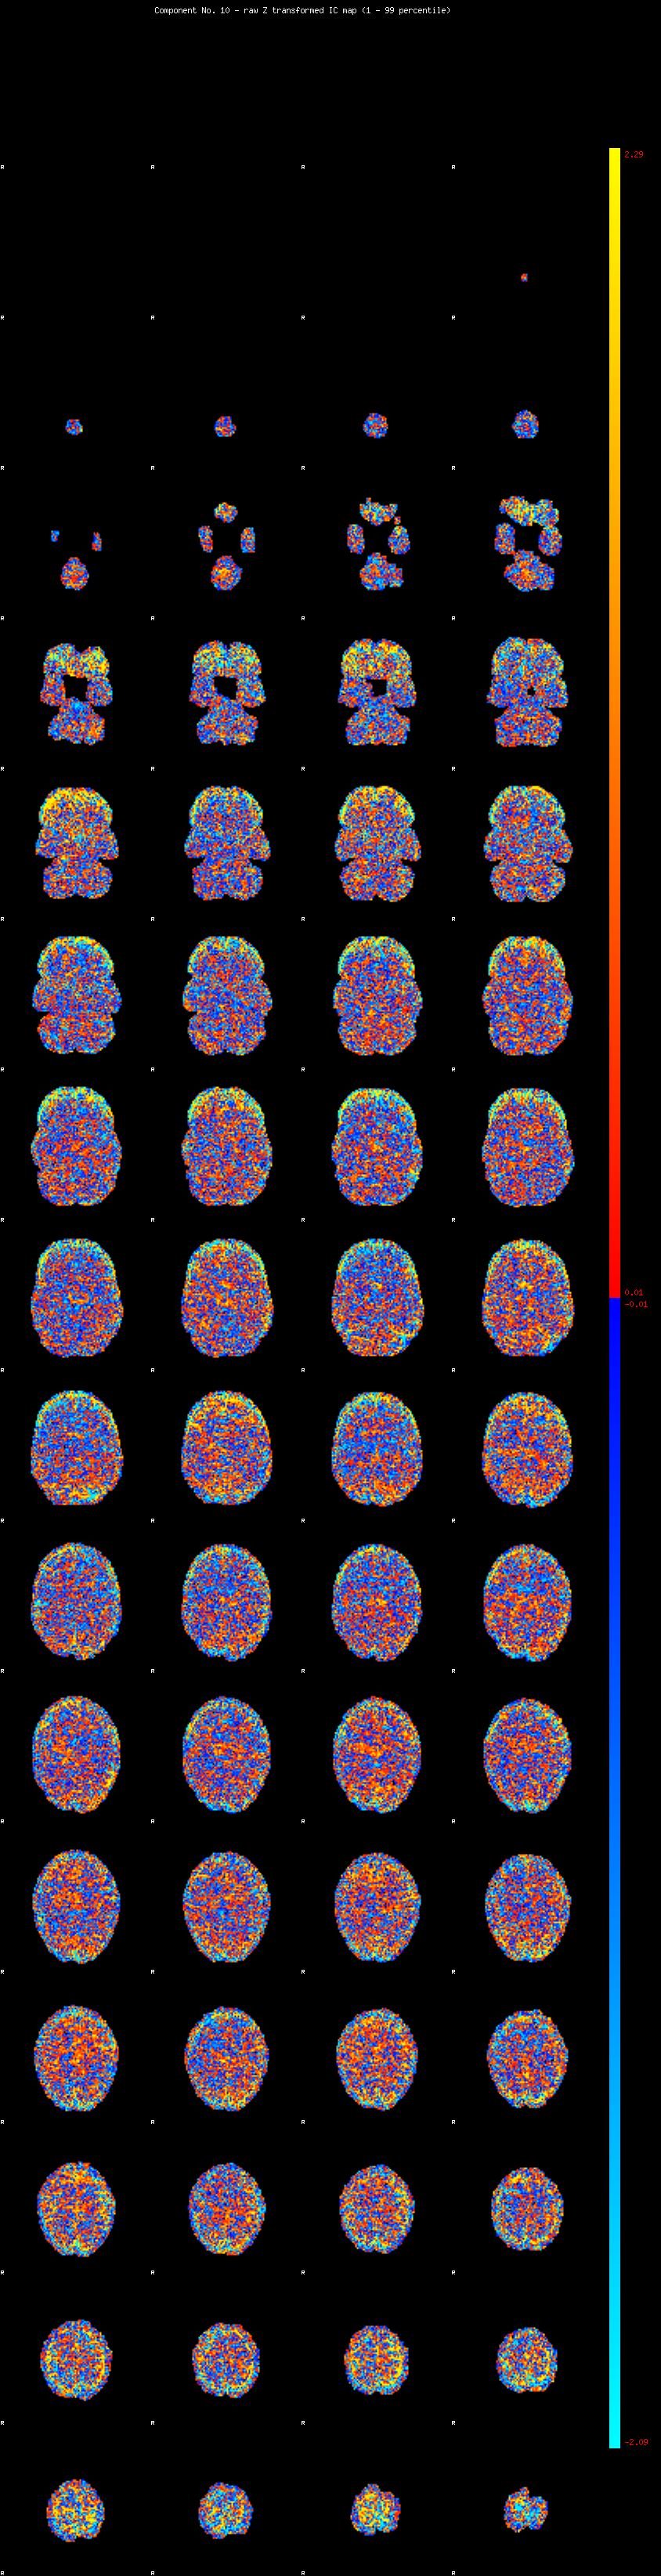

IC_10 Mixture Model fit

Means : -0.000000 2.494467 -2.609873

Vars : 1.000000 1.931745 1.395445

Prop. : 0.897475 0.063250 0.039275